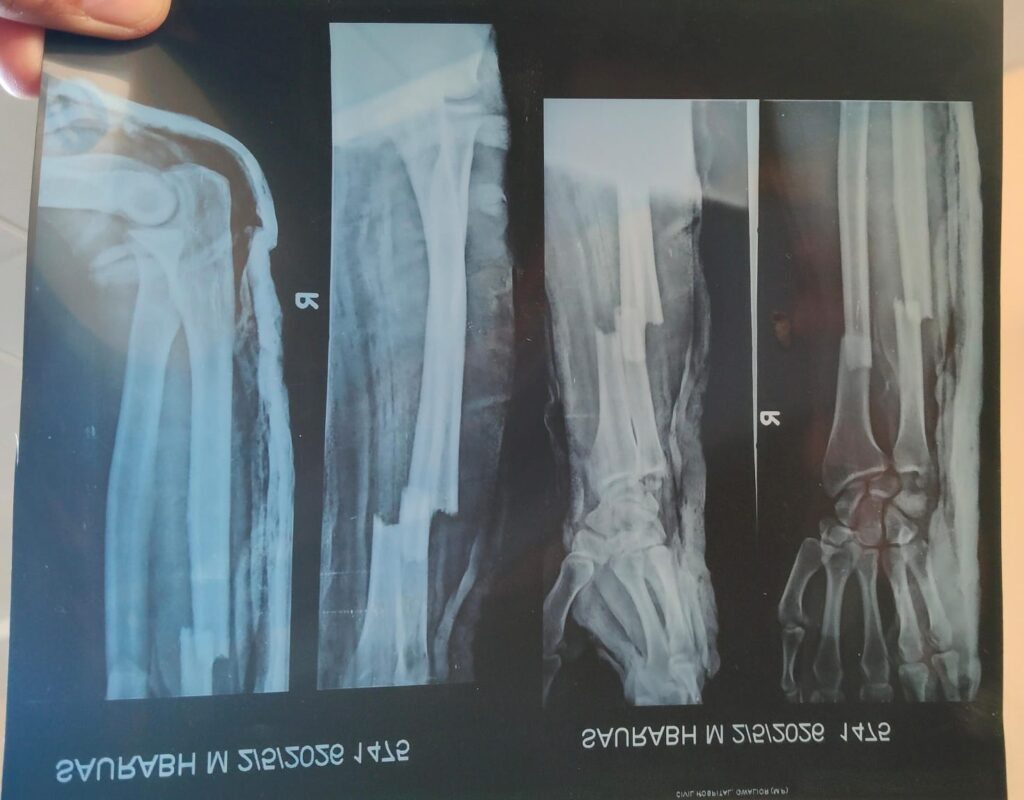

During a physical training session, Sourabh, a visually impaired player from the Uttar Pradesh Goalball team, reportedly suffered a compound fracture. According to sources, the accident occurred when players were asked to run a 100-metre sprint without any safety measures or proper supervision. It is further alleged that athletes were instructed to jump forward without bending their knees—an unsafe technique, particularly dangerous for blind players who depend entirely on verbal instructions.